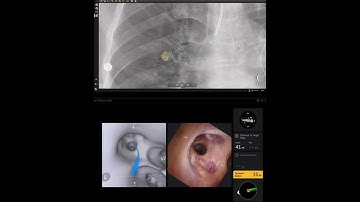

Direct visualization of the lung nodule #bronchoscopy